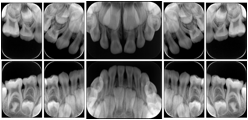

Intra-oral radiography typically involves acquisition of multiple images of various parts of the dentition. Many digital radiographic systems offer customized templates that are used for displaying the images in a study on the screen. These templates may also be referred to as mounts or view sets. The Structured Display Object represents a standard method of encoding and exchanging the layout and intended display of Structured Displays. A structured display object created in this manner could be stored with a study and exchanged with images to allow for complete reproduction of the original exam.

In most standard cases, images are oriented in structured layouts. These structured displays are useful to be shared between providers for reference purposes.

Table OO.1.1-1 shows structured display standard templates, where Viewset ID is based on the Japanese Society for Oral and Maxillofacial Radiology (JSOMR) classification provided by JIRA (Japan Medical Imaging and Radiological Systems Industries Association, www.jira-net.or.jp). Expected or typical teeth to be imaged location, region and designation codes are based on ISO 3950-2010, Dentistry - Designation system for teeth and areas of the oral cavity. For all the hanging protocols listed in OO.1.1-1, the value to use for Hanging Protocol Creator (0072,0008) is "JSOMR" and the value to use for Hanging Protocol Name (0072,0002) does not include "JSOMR" (e.g., "DL-S001A", not "JSOMR DL-S001A").